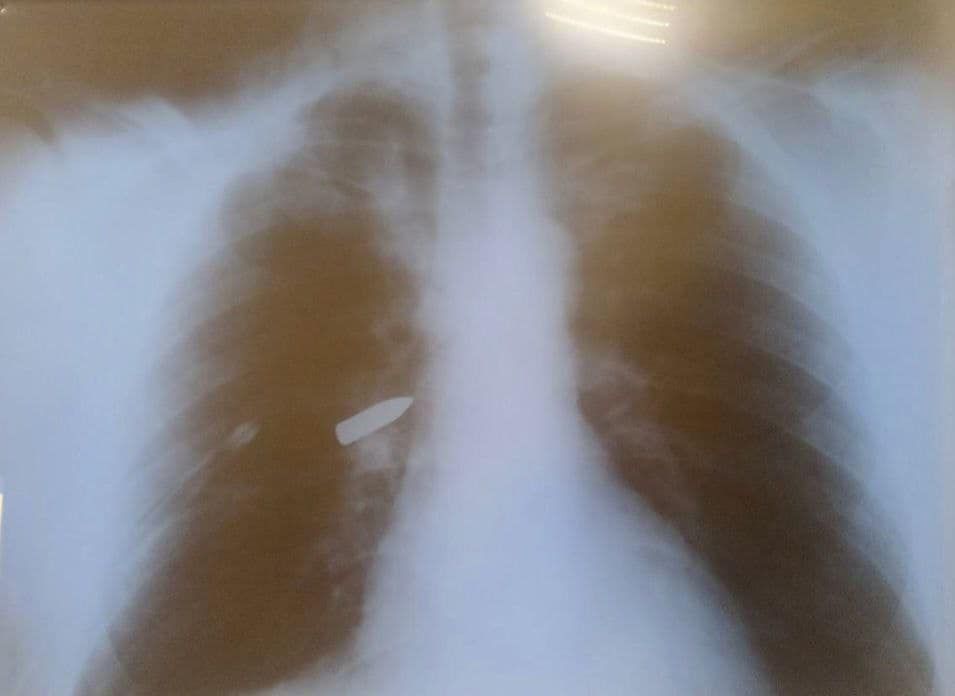

Привезли военного в одну из больниц Днепра. В легких раненого застрял пуля. Хирурги взялись за сложную операцию, хотя шансов на спасение было мало. Медики разработали план, но он был рискованным.